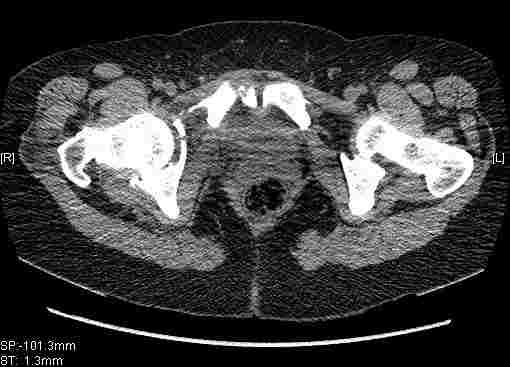

Удалось сегодня вывести пациентку в соседнюю больницу, где есть кт. Срезы сделаны только горизонтальные.